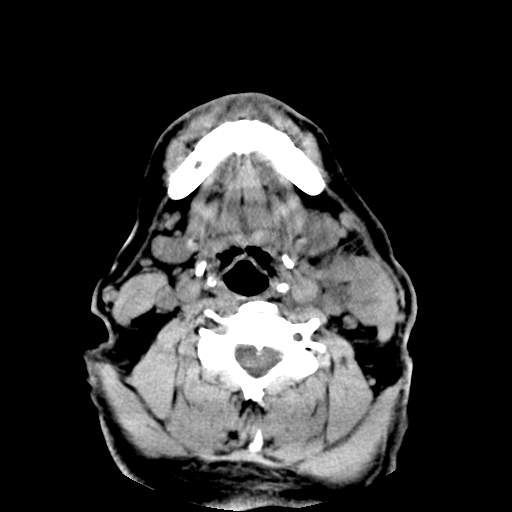

以下是引用卜一在2007-8-6 21:23:00的发言:[br]定位:左侧胸锁乳突肌内侧 颌下腺下后方。特征:弥漫性生长 软组织密度肿块,界限不清,内隐约见低密度坏死。考虑:神经源性肿瘤或血管源性肿瘤。

以下是引用wangzhanshuang在2007-8-6 21:08:00的发言:[br]腮腺混合瘤